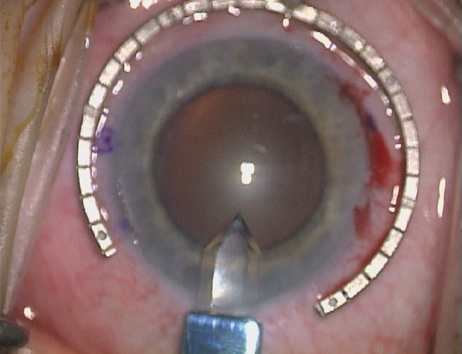

Case 1 is a 68-year-old male who presented for right cataract surgery. His refraction was −1.00 +2.25 × 80 and was recorded as reliable, consistent with his modest cataract density. Keratometry readings were 44.75 × 75 and 43.00 × 165. Corneal topography confirmed slightly more than 2.00 D of regular and slightly oblique cylinder. Consulting the nomogram, a plan was devised for a pair of LRIs to be centered over the 75-degree axis, with each incision delineating 45 degrees of arc. A single plane phaco incision was used and maintained at a size of less than 3.2 mm (Figs. 811).

Fig. 10. The single footplate diamond blade is inserted perpendicular to the corneal surface and at the peripheral most extent of clear corneal tissue. In this case, the nomogram calls for arcuate incisions of 45 degrees. Therefore, the incision is begun approximately 22.5 degrees to one side of the broad hash mark. (Reprinted from Hardten DR, Lindstrom RL, Davis EA. Phakic Intraocular Lenses: Principles and Practice. Thorofare, NJ: SLACK Incorporated, 2004, with permission.)